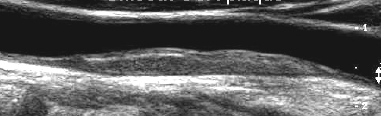

identify what type of plaque

what are their characteristics?

all Heterogeneous - mixed echoic pattern. Homogeneous is- uniform plaque texture